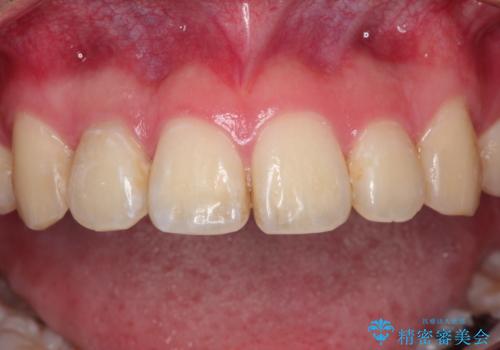

根管治療を含め、オールセラミッククラウンにて修復治療を行っております。

今回は歯冠修復にe-maxプレスクラウンを使っています。